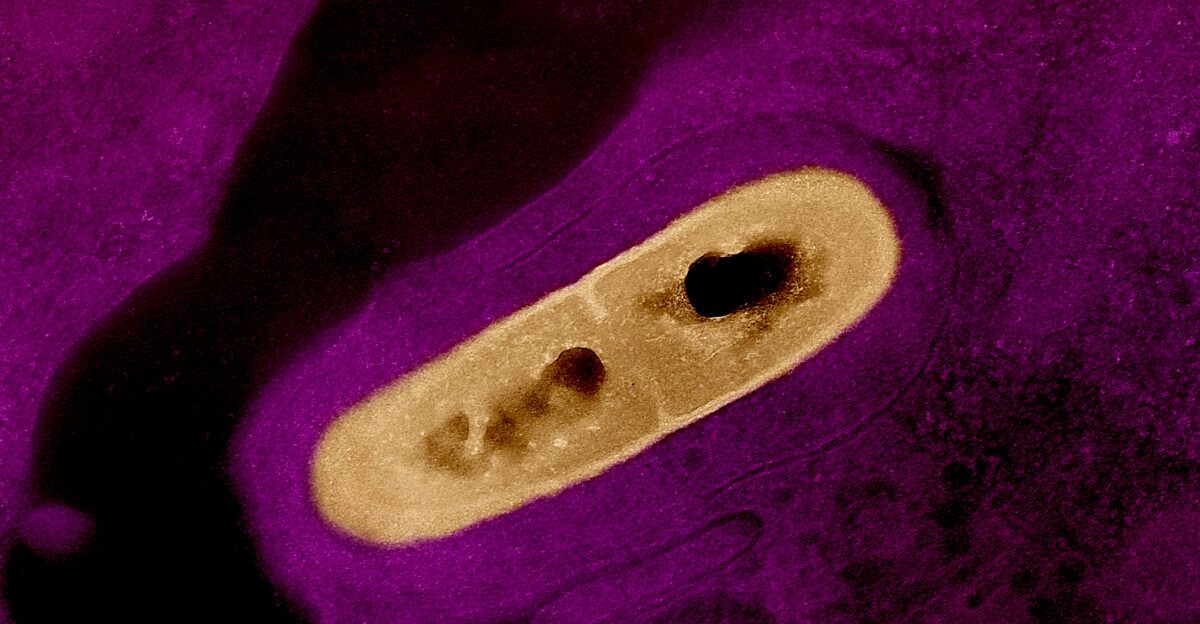

The Bacteria That Thrives in Cold

Listeria monocytogenes is uniquely dangerous because it defies conventional food safety assumptions. “It thrives where others can’t—in the fridge,” said Dr. Aaron Mills, a CDC food safety expert. Unlike most pathogens, Listeria survives and multiplies in cold storage, making refrigeration no safeguard.

“Listeria is relentless, especially for the elderly and pregnant,” Dr. Alvarez noted. The bacteria can cause meningitis or pregnancy complications once it enters the bloodstream. Symptoms may not appear for up to 70 days, leaving families unaware of danger long after meals are consumed.